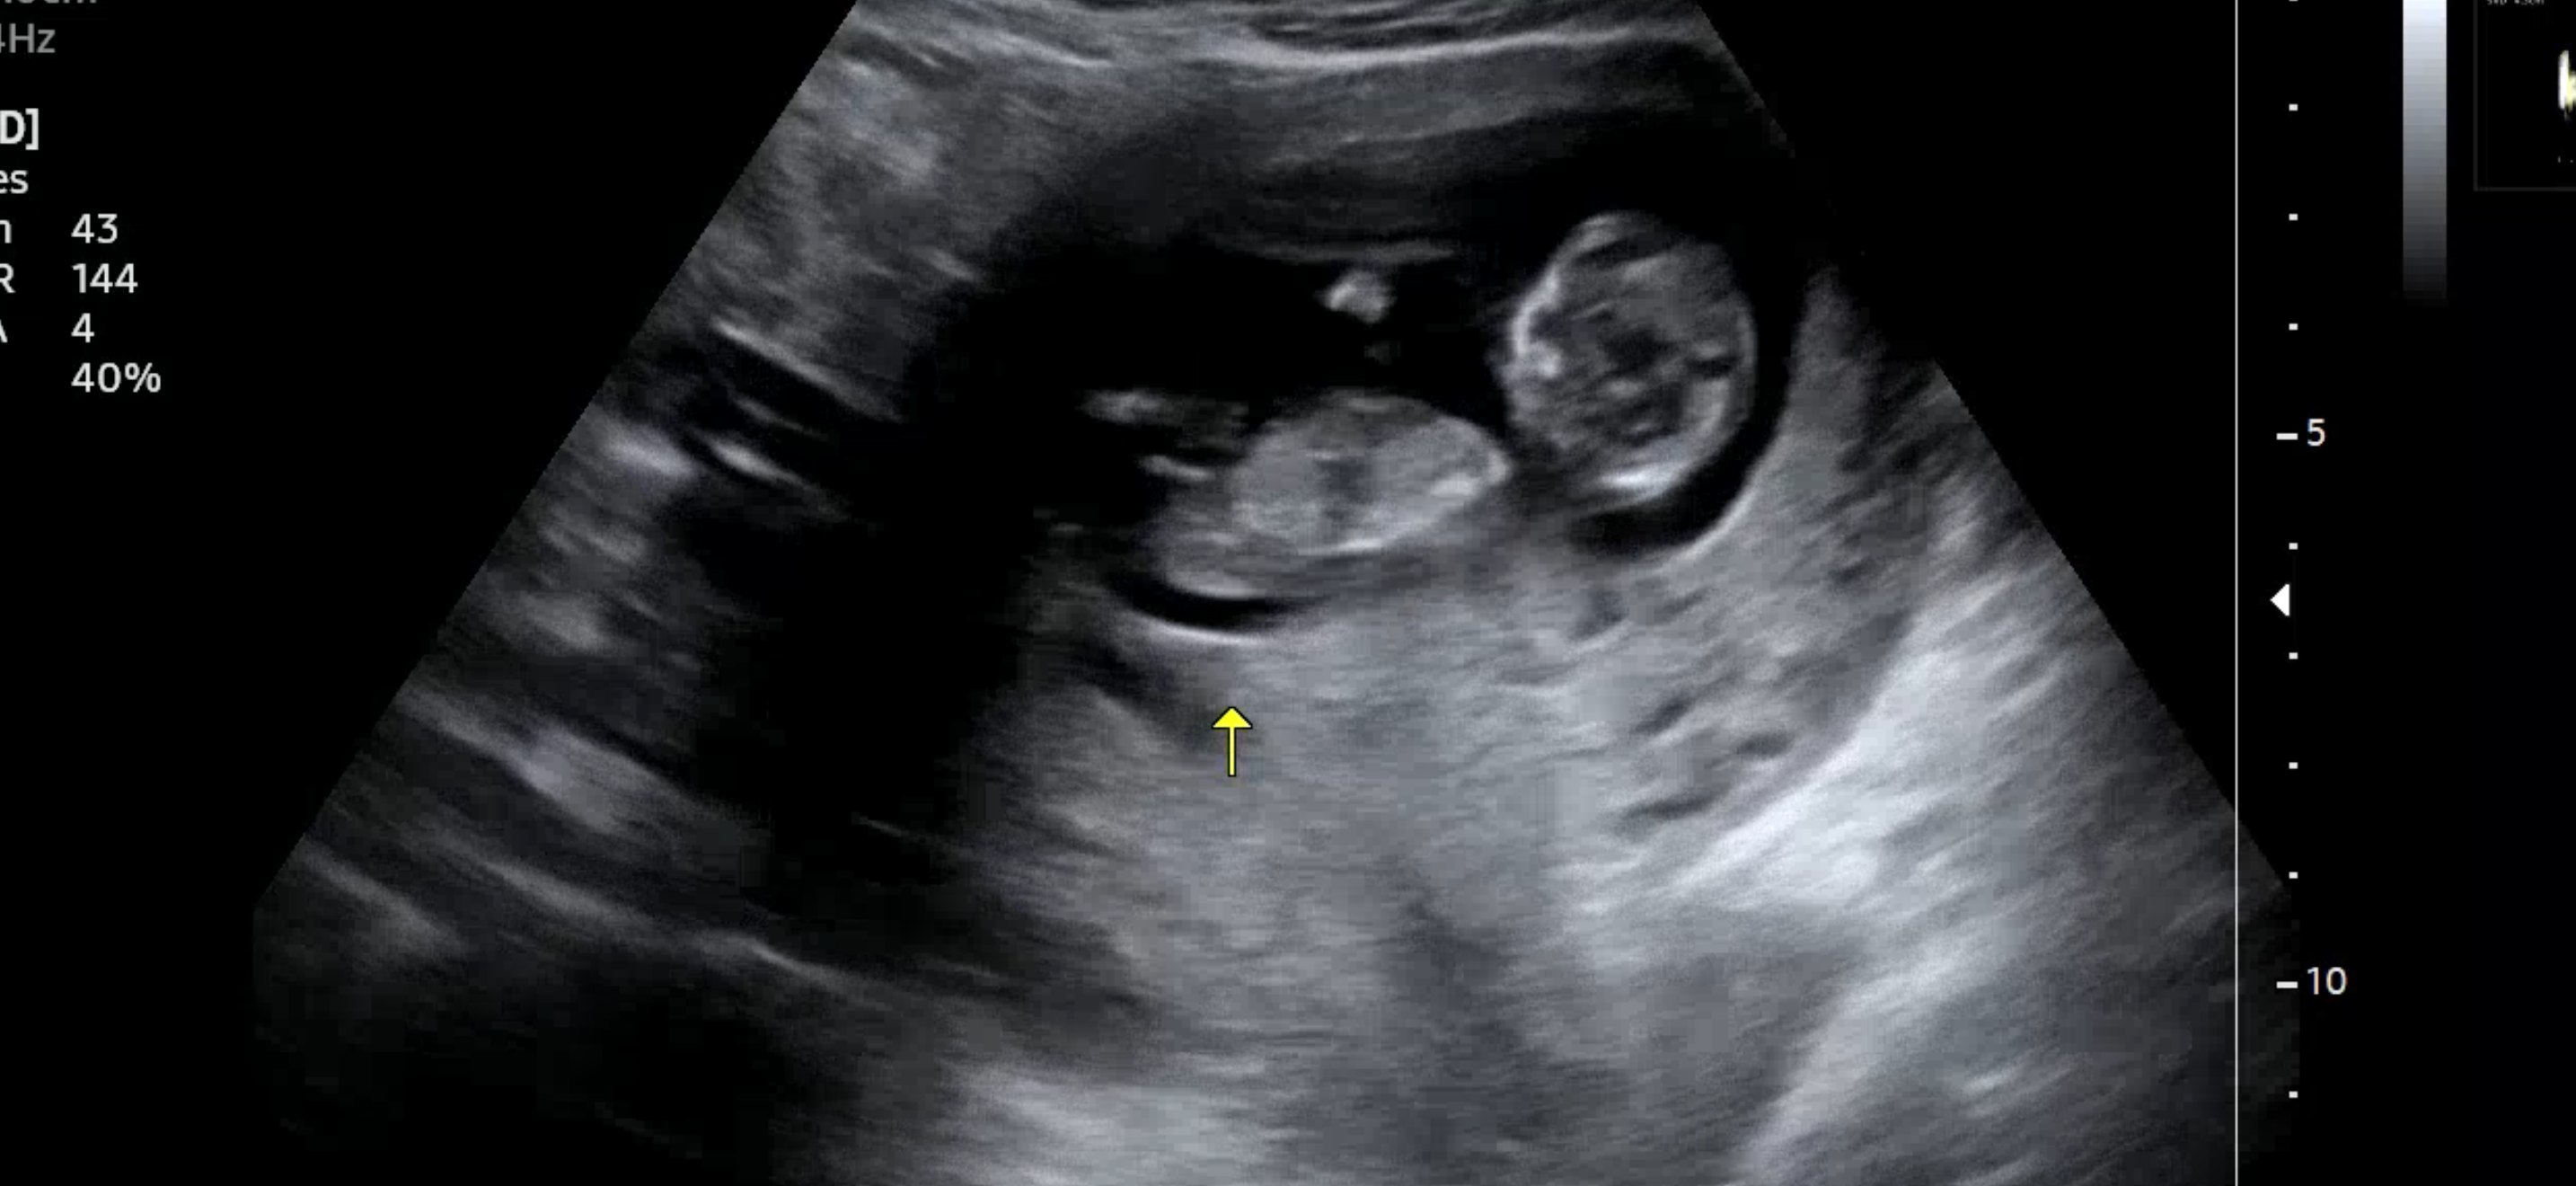

12주 0일 각도법고수님들 부탁드려요!

봐도 영 모르겠네여... 뭘로 보이시나요..?ㅜㅜ